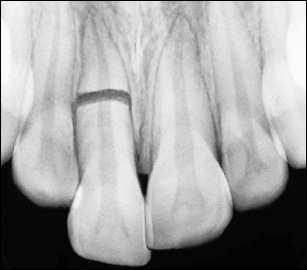

Στην περίπτωση της εμβύθισης εξετάζουμε ακτινογραφικά αν έχει τραυματιστεί το οδοντικό σπέρμα του μόνιμου διαδόχου δοντιού.

Αν δεν έχει νεκρωθεί με το χρόνο επανέρχεται στην αρχική του θέση. Στην περίπτωση ολικής εκγόμφωσης παιδικού δοντιού δεν το βάζουμε πίσω στην θέση του, επικοινωνούμε με τον παιδοδοντίατρο για την εκτίμηση της κατάστασης.

016 Η σημασία της στοματικής υγιεινής και ορθοδοντικής πρόληψης

Αν το νεογιλό δόντι νεκρωθεί γεγονός πού φαίνεται από την αλλαγή χρώματος και δημιουργηθεί απόστημα ή συρίγγιο πρέπει να θεραπευθεί για να μην χαλάσει η οδοντική επιφάνεια του μόνιμου διαδόχου δοντιού.

β. Τραύμα στα μόνιμα δόντια Είναι πολύ συχνό στην ηλικία των 7-8 ετών που το παιδί έχει ήδη τα μόνιμα μπροστινά του δόντια. Μπορεί να συμβεί:

β1--κάταγμα μύλης

Αν βρεθεί το σπασμένο κομμάτι καλό είναι να το βάλουμε σε φυσιολογικό ορό ή σε νερό. Επικοινωνούμε με τον θεράποντα ιατρό και ή γίνεται συγκόλληση του κατεαγότος τμήματος ή συμπληρώνεται το έλλειμμα με ειδικά οδοντιατρικά υλικά εφόσον εξετάσουμε πρώτα τη θέση της γραμμής του κατάγματος σε σχέση με το οδοντικό νεύρο.

β2--κάταγμα ρίζας Αν διαγνωσθεί ακτινογραφικά κάταγμα ρίζας αυτό εκτιμάται από τον θεράποντα ιατρό. Γλωσσική ναρθηκοποίηση και ενδοδοντική θεραπεία βοηθούν στην περαιτέρω εξέλιξη